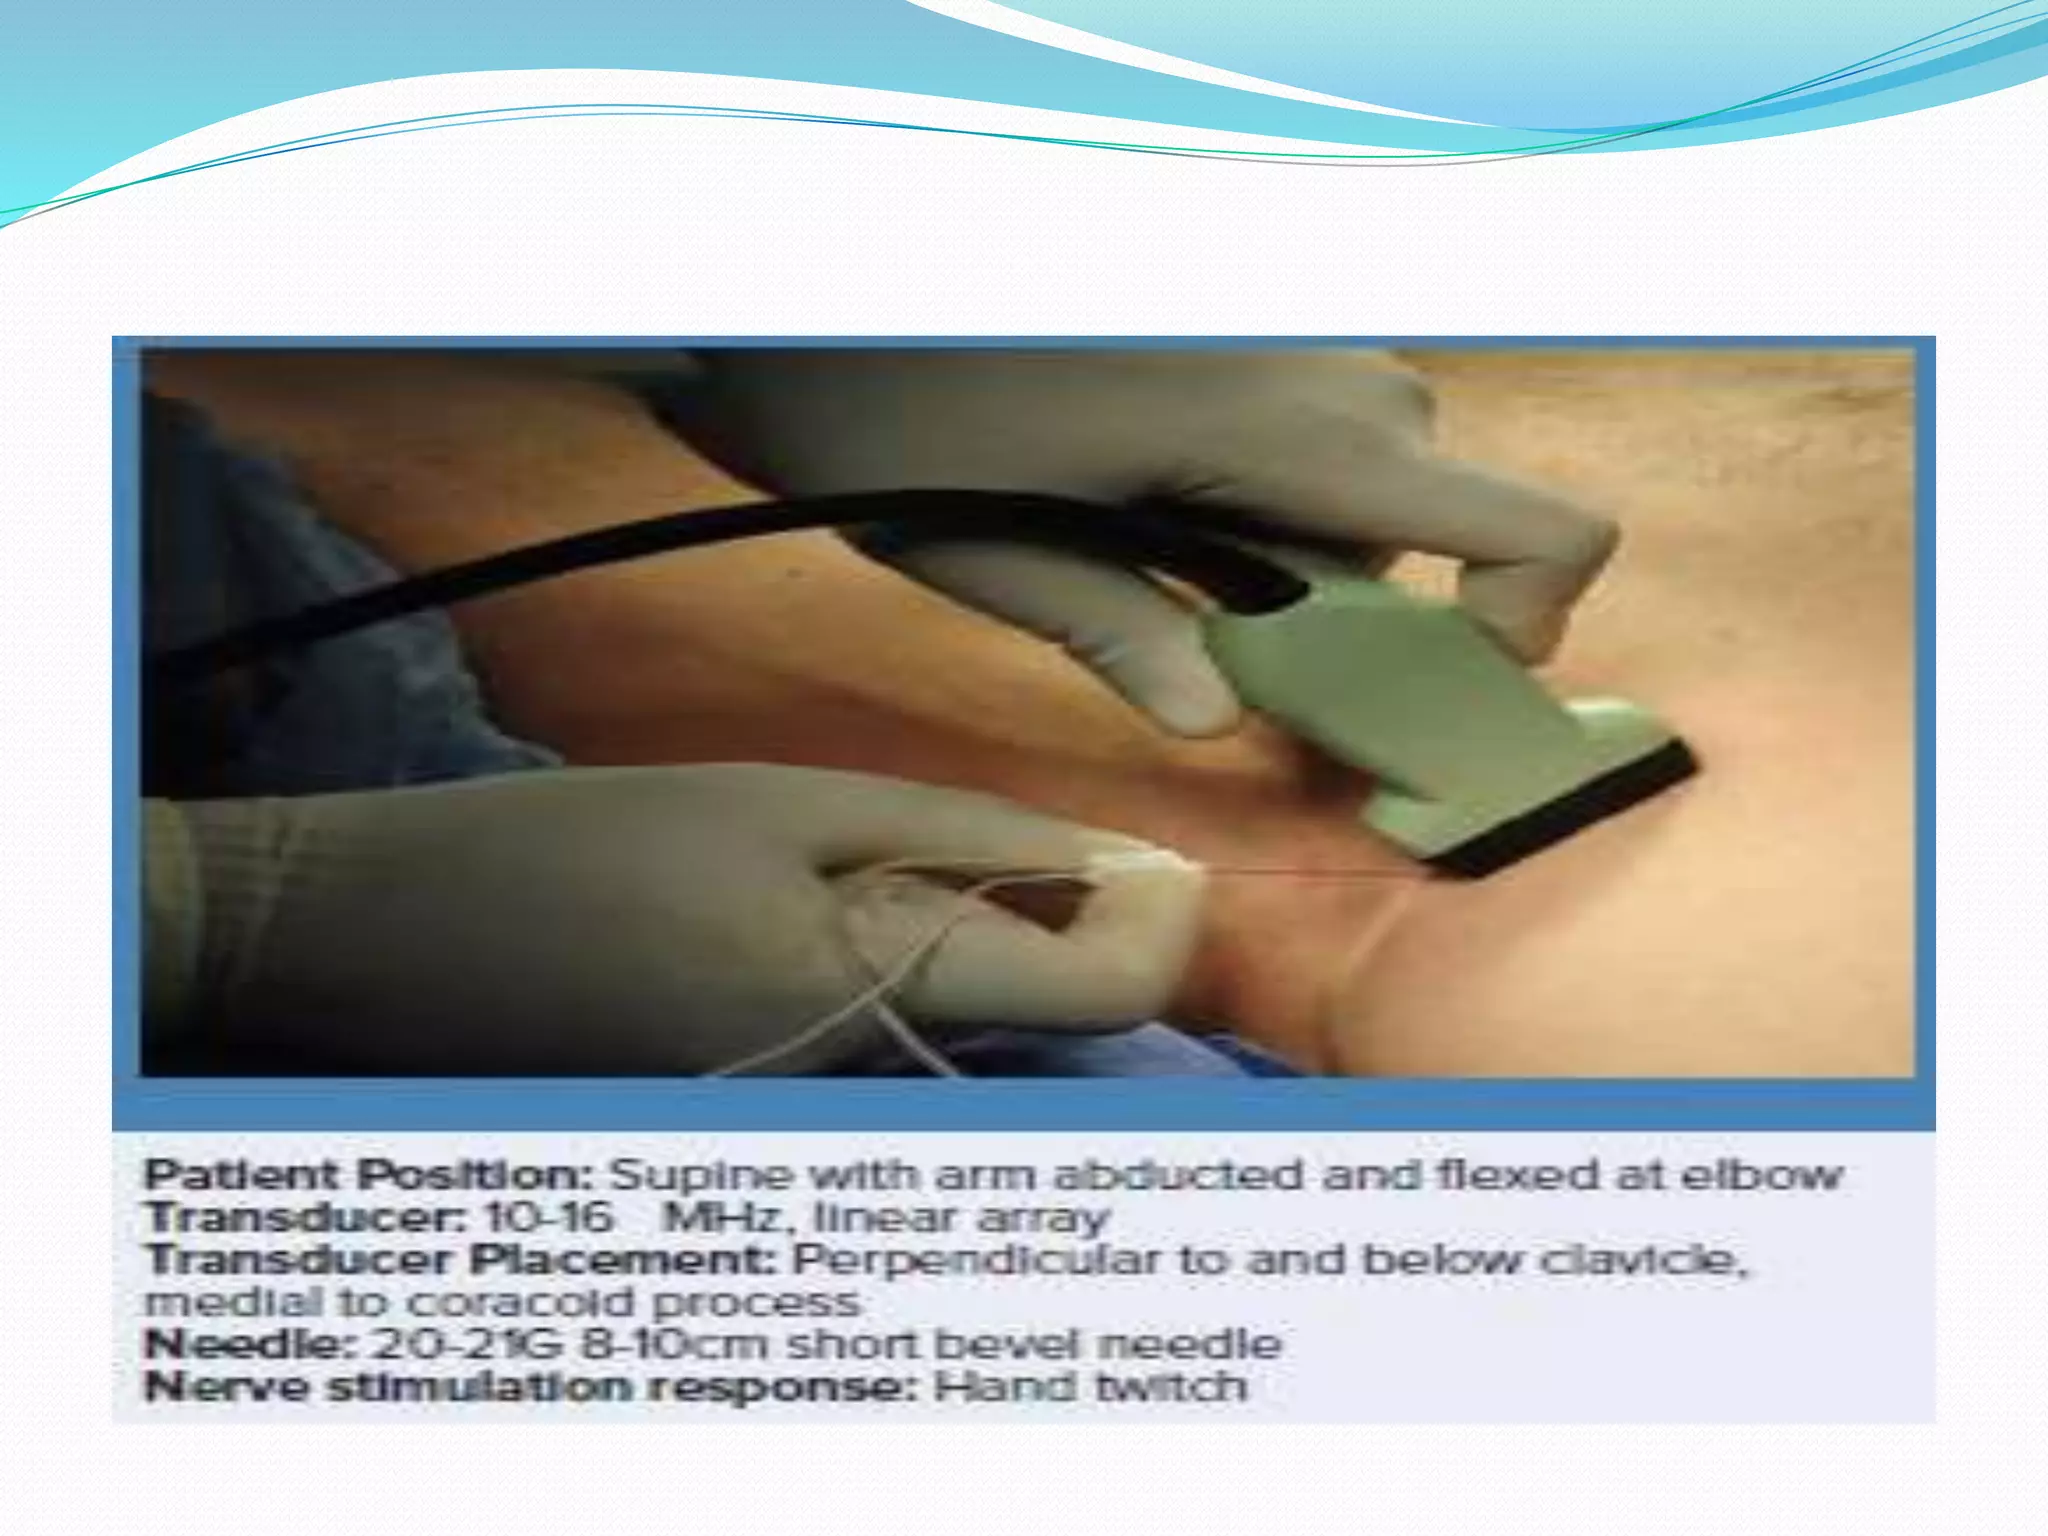

This document provides an overview of brachial plexus anatomy and techniques for brachial plexus nerve blocks. It begins with a description of the brachial plexus formation from cervical and thoracic nerve roots and its branching pattern. Four main approaches for brachial plexus nerve blocks are described: interscalene, supraclavicular, infraclavicular, and axillary. Details are provided on the anatomy and techniques for performing interscalene and supraclavicular brachial plexus blocks. Ultrasound guidance is discussed as an advancement which allows real-time visualization of needle and nerve. Complications are also summarized.